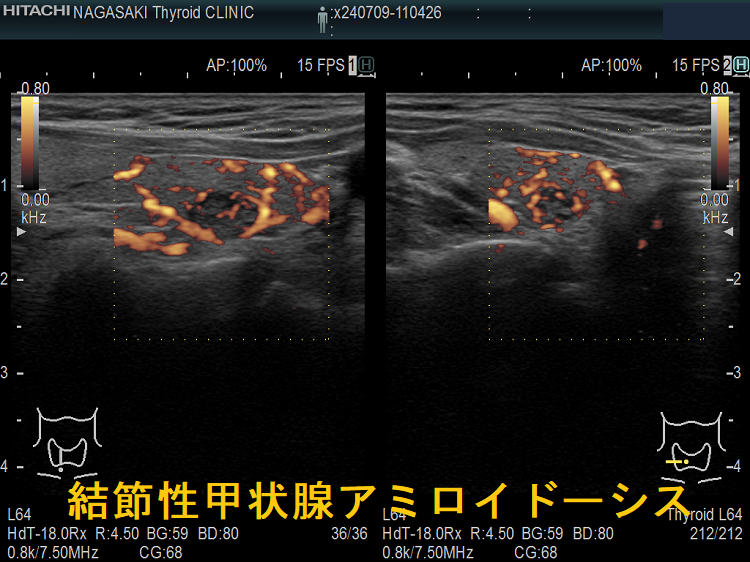

謎の結節性甲状腺アミロイドーシスを鹿児島大学が甲状腺学会で複数回、さらに大分大学も論文で報告しています。超音波(エコー)検査上、見かけは甲状腺腫瘍、境界不明瞭・不均質な低エコー領域で、石灰化も伴う。穿刺細胞診で腫瘍成分はなく、アミロイドのみが見つかるも、アミロイドーシスをおこす他の病気が全くないとの事です。

大分大学の報告は多結節性甲状腺腫の形態です[Acta Pathol Jpn. 1992 Mar;42(3):210-6.]。

橋本病に合併した結節性甲状腺アミロイドーシスの病理組織標本では、